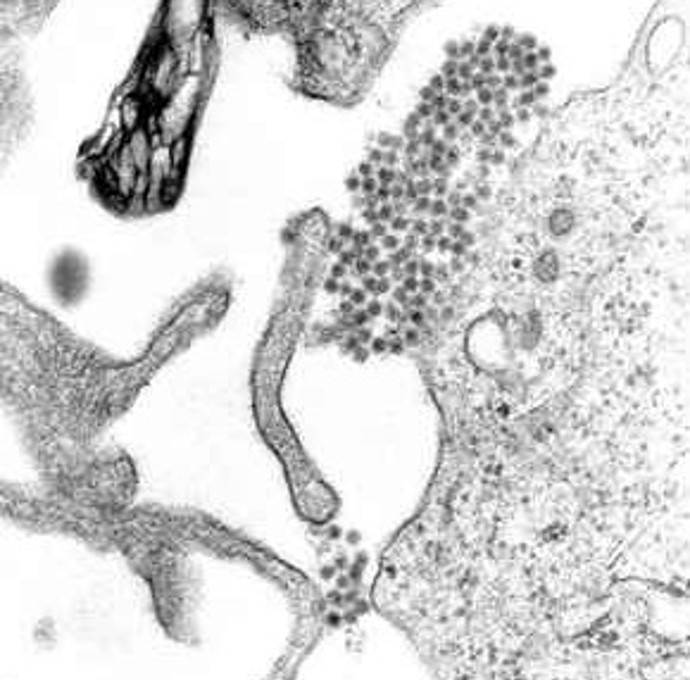

Virus dengue způsobuje stejnojmennou horečku, kterou provází obrovské bolesti a pacient neuvěřitelně trpí. Mimo jiné má pocity zlámaných končetin. První zmínky o nemoci, kterou přenášejí komáři, pocházejí z roku 1779, po druhé světové válce se stala celosvětovým problémem a dnes je běžná ve více než 110 zemích světa. Zdroj: Unviersity of South Carolina Biomedical Sciences Public Domain